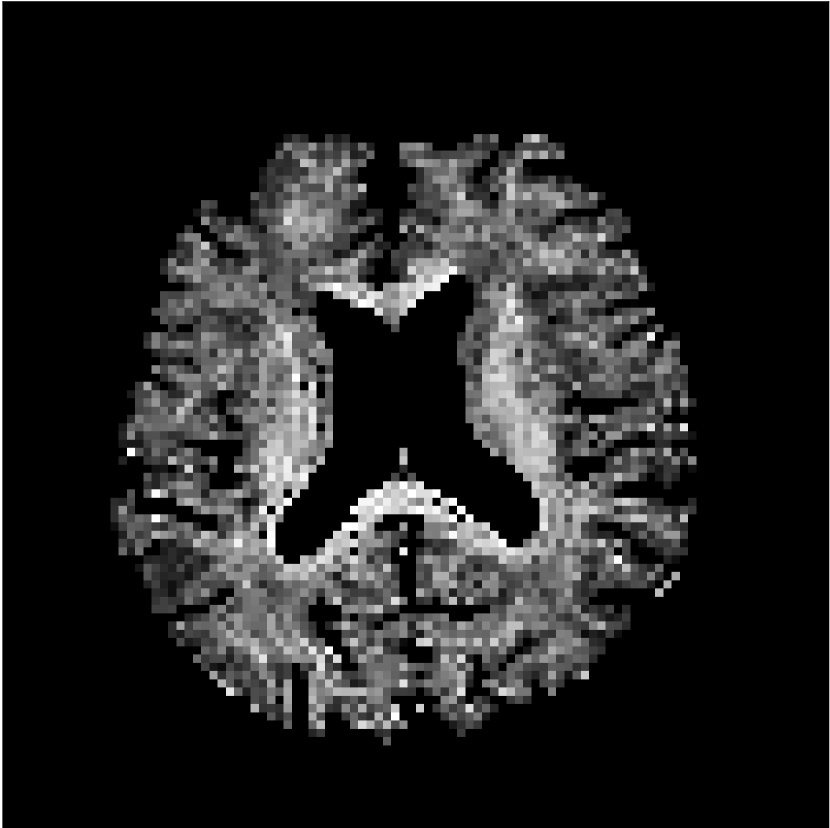

Figure 8 shows examples of non-diffusion-weighted images before and after processing. The raw images (Raw) served as the input for the magnitude deep learning (MCNN) and complex deep learning (CCNN) methods.

Raw 𝐱tsubscript𝐱𝑡\mathbf{x}_{t}

MCNN, fθ^(𝐱t)subscript𝑓^𝜃subscript𝐱𝑡f_{\hat{\theta}}\left(\mathbf{x}_{t}\right)

MCNN Resid., Ric(𝐱t)fθ^(𝐱t)Ricsubscript𝐱𝑡subscript𝑓^𝜃subscript𝐱𝑡\text{Ric}(\mathbf{x}_{t})-f_{\hat{\theta}}\left(\mathbf{x}_{t}\right)

CCNN, fθ^(𝐱t)subscript𝑓^𝜃subscript𝐱𝑡f_{\hat{\theta}}\left(\mathbf{x}_{t}\right)

CCNN Resid., Ric(𝐱t)fθ^(𝐱t)Ricsubscript𝐱𝑡subscript𝑓^𝜃subscript𝐱𝑡\text{Ric}(\mathbf{x}_{t})-f_{\hat{\theta}}\left(\mathbf{x}_{t}\right)

No PF

5/8 PF

Figure 8: Examples of non-diffusion-weighted images from in vivo data at b=0𝑏0b=0 s/mm2. Artifacts in the Raw image, 𝐱tsubscript𝐱𝑡\mathbf{x}_{t}, are corrected by the MCNN and CCNN models, fθ^(𝐱t)subscript𝑓^𝜃subscript𝐱𝑡f_{\hat{\theta}}(\mathbf{x}_{t}). Also shown are the residuals between the CNN corrections and the original Raw image with Rician bias correction Ric(𝐱t)Ricsubscript𝐱𝑡\text{Ric}(\mathbf{x}_{t}) [10]. The Gibbs artifacts removed by the methods are observed in the residuals. The MCNN method introduces some banding artifacts at the PF 5/8ths factor that are not present in the CCNN method.

Both methods remove artifacts, but the MCNN method allows residual rippling artifacts to pass through in the presence of partial Fourier. These rippling artifacts are not present in the CCNN method.